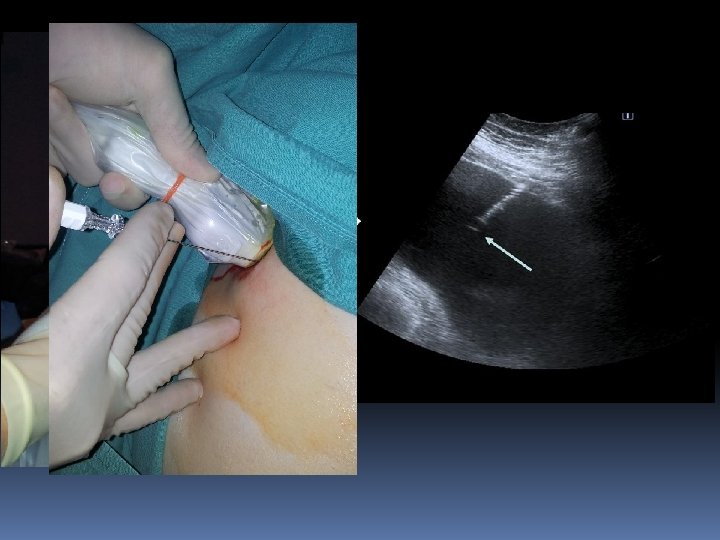

TECNICAS DE DRENAJE DE COLECCIONES Técnica trocar: • • Punción única Más rapida Menos segura Grandes colecciones Técnica Seldinger: • Menos rápida • Muy segura • La más utilizada

Povidona yodada Fisiológico 2 jeringuillas de 20 cc Gasas Bisturí Lidocaína 2% Aguja de 19 G Guía extrarrígida de soporte Dilatadores fasciales (7, 8 , 9) Catéter hidrofílico pig-tail 8 F

ELECCION DEL PUNTO DE ENTRADA • Siempre guiados por imagen ( US o TC ) SE • DESACONSEJA MARCAJE PARA PUNCION DIFERIDA Siempre por el borde superior de la costilla • Siempre el punto más declive • Evitar accesos dorsales posteriores si se puede • Evitar el borde medial de la escápula